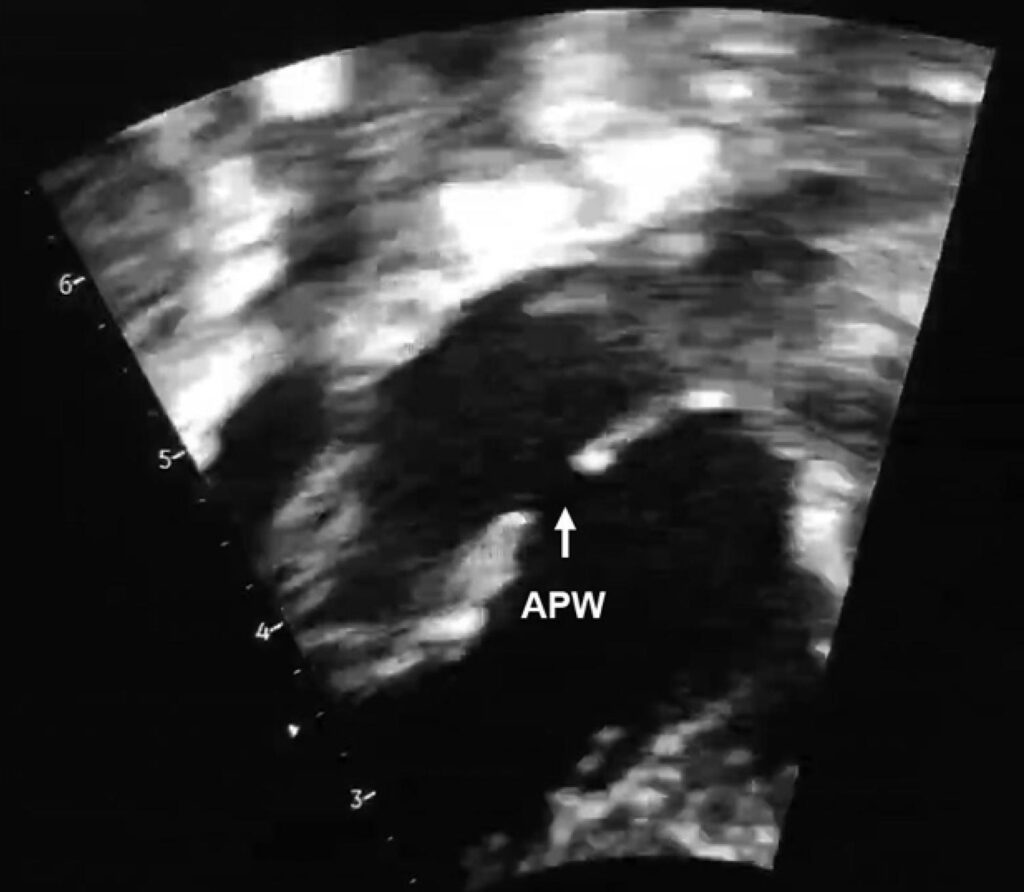

Figure 1

– Echocardiogram showed a large 5.0 mm APW (white arrow). APW: Aortopulmonary Window.